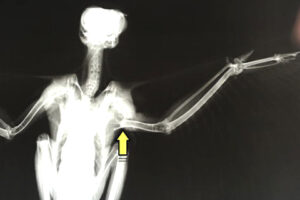

上腕骨が真っ二つ!

レントゲンを撮ってみると、左の上腕骨(写真では、右側の翼の根本。矢印の部分)が真っ二つに折れていました。事故直後は出血もひどかったらしく、血液の濃度が正常値の半分以下にまで下がっていました。